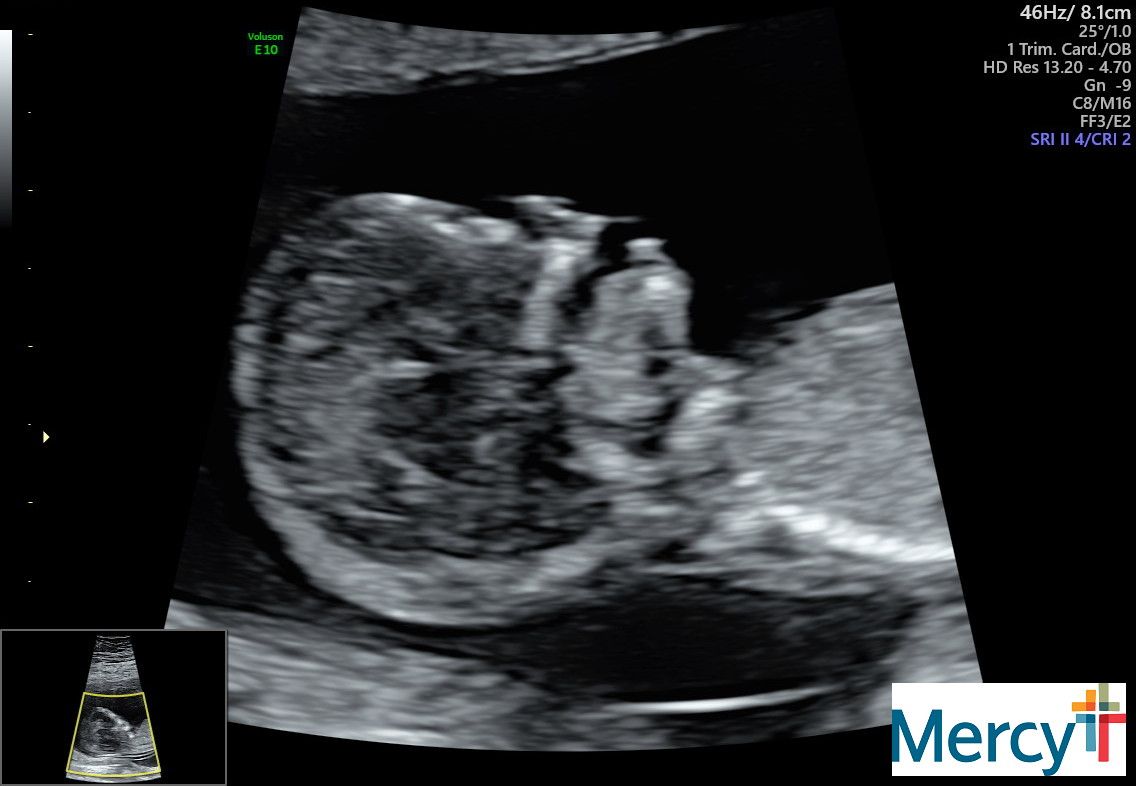

September 25: 12 weeks

We started off the meeting with a genetic counselor, named Porter. He was super helpful and it was great to get a big picture with Logan there. Next, they took some blood and sent us off to the ultrasound. It was really fun to see that baby squirm around for a good 30 minutes! They were sticking out their tongue and jumping all over. Soooo fun! We will be back here on October 22 (16 weeks). After that we will be here every Thursday from 16-28 weeks!